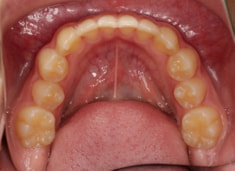

検査時のレントゲン分析では、上下顎の関係は、上顎の劣成長があり下顎前突傾向という値がでておりましたが、前歯ジャンプ後はフェイスマスクの効果もあり、上下顎の関係は正常化しています。

上顎が若干優位になっていますので、今後の下顎の成長のための貯金になっているくらいです。